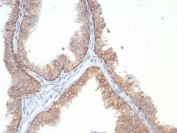

IHC staining of FFPE human prostate tissue with IL-18 antibody (clone IL18/4628) at 2ug/ml. HIER: boil tissue sections in pH 9 10mM Tris with 1mM EDTA for 20 min and allow to cool before testing.